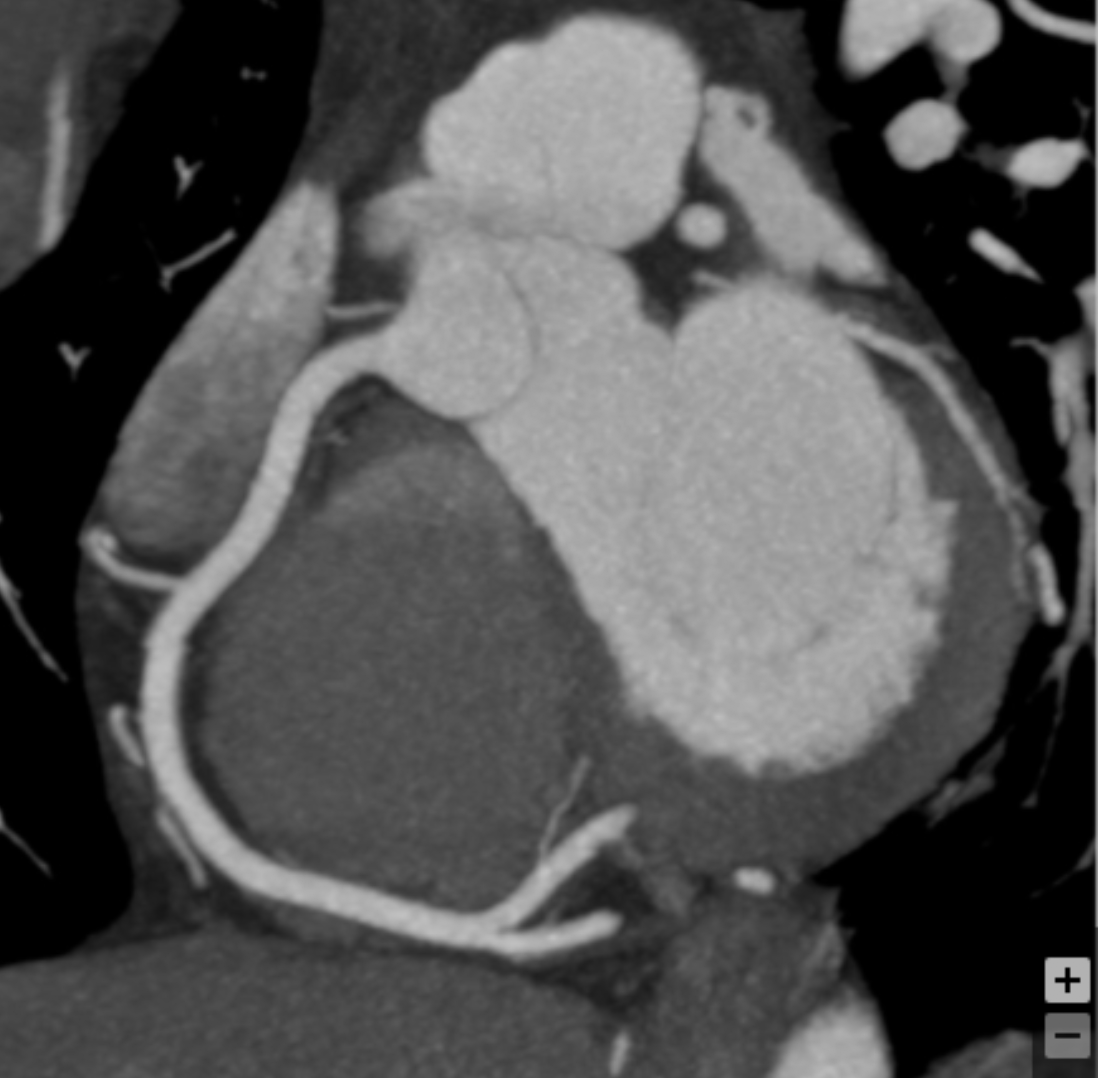

How many high-grade luminal stenoses ( >70%) are present?

1

Describe the findings and next step:

Myocardial bridging - Reassurance